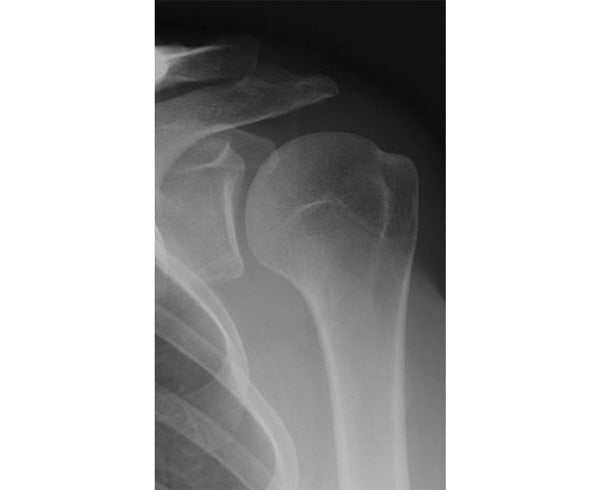

Glenohumeral Arthritis

Symptoms of GH joint arthritis include shoulder pain, stiffness, end range of motion pain (pain that worsens towards the end of your shoulder range), and pain at night. The pain is often described as a “deep ache” and becomes progressively worse over time. You may hear and feel a grinding sensation as you move your shoulder.